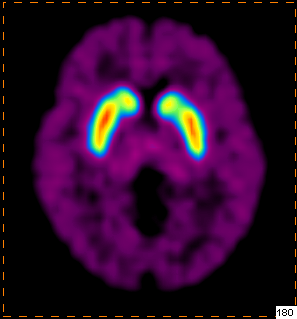

脑部多巴胺受体显像辅助诊断帕金森病

患者,男性,35岁

临床怀疑帕金森病

我科使用11C-CFT进行脑部多巴胺受体显像

PET/CT示:

双侧尾状核、双侧壳核放射性摄取对称,未见明显减低

根据PET图像,最终排除帕金森病